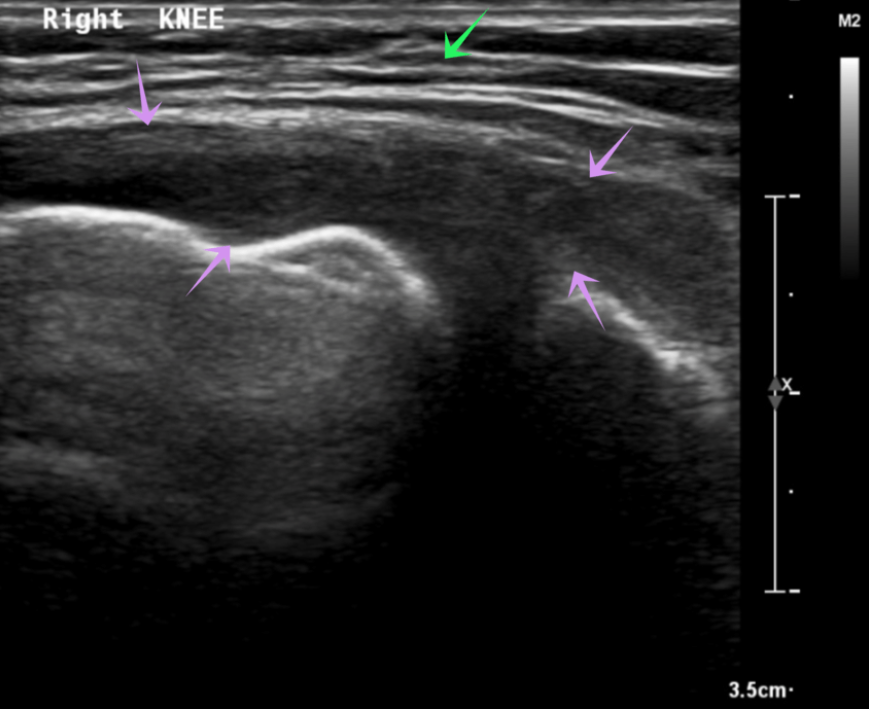

Right knee ultrasound showing large join effusion (purple arrows) and hyperaemia with debris (green arrow) suggestive of septic arthritis.

Ultrasound is effective in detecting and evaluating joint effusions (fluid buildup) in the knee. This helps in diagnosing conditions like osteoarthritis and inflammatory arthritis and in guiding therapeutic aspirations.